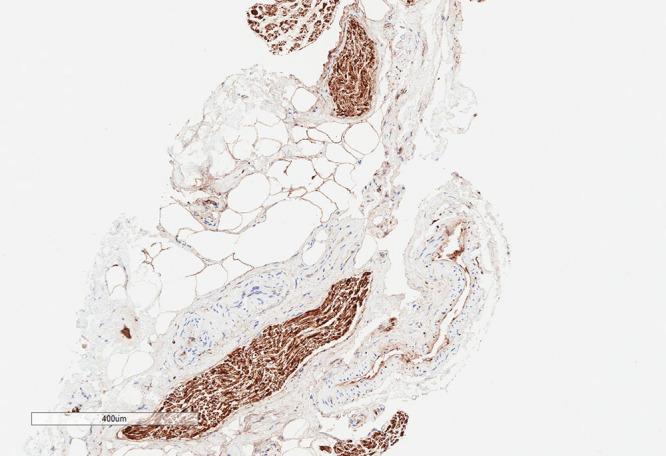

While newer breast reconstruction approaches utilizing nipple-sparing mastectomy (NSM) techniques and immediate reconstruction can provide excellent aesthetic outcomes, absent postoperative sensation remains a major limitation. Here, we present a novel technique for implant reconstruction combining the latest advances in breast oncologic, reconstructive, and peripheral nerve surgery to improve sensory outcomes. Sixteen women (31 breasts) underwent NSM and prepectoral, direct-to-implant reconstruction. During NSM, careful dissection was performed along the lateral aspect of the breast to preserve any visible intercostal nerves. When nerves could be preserved without compromising oncologic safety, they were left intact within the subcutaneous tissue of the lateral mastectomy skin flap. Nipple/areolar complex (NAC) neurotization was also performed utilizing allograft coapted from transected T or T lateral intercostal nerves to subareolar nerves identified at the completion of the mastectomy. Of the 12 women (23 breasts) with at least 3 months' follow-up, NAC 2-point discrimination was preserved in 20 breasts (87%), was worse in 2 breasts (9%), and had actually improved in 1 breast (4%). All patients had intact sensation to light touch throughout the majority of, if not their entire, reconstructed breasts. None of the women developed dysesthesias or neuromas. Nerve grafting in conjunction with careful nerve preservation at the time of NSM and implant-based breast reconstruction is safe and effective with a 90% rate of preserved sensation. With longer follow-up, continued return of sensation or possibly improved sensation from baseline can be reasonably anticipated.

虽然采用保留乳头的乳房切除术(NSM)技术和即刻重建的新型乳房重建方法可以提供出色的美学效果,但术后感觉缺失仍然是一个主要限制。在此,我们提出一种用于植入物重建的新技术,结合了乳房肿瘤学、重建外科和周围神经外科的最新进展,以改善感觉效果。16名女性(31个乳房)接受了NSM和胸肌前直接植入物重建。在NSM过程中,沿着乳房外侧进行仔细解剖,以保留任何可见的肋间神经。当神经可以在不影响肿瘤安全性的情况下保留时,将其完整保留在乳房外侧切除皮瓣的皮下组织内。还利用从横断的T或T₁₂肋间神经截取的同种异体移植物与乳房切除完成时在乳晕下识别出的神经进行乳头/乳晕复合体(NAC)神经吻合。在12名至少随访3个月的女性(23个乳房)中,20个乳房(87%)的NAC两点辨别觉得以保留,2个乳房(9%)变差,1个乳房(4%)实际上有所改善。所有患者在大部分(如果不是全部)重建乳房中对轻触的感觉均完整。没有女性出现感觉异常或神经瘤。在NSM和基于植入物的乳房重建时,结合仔细的神经保留进行神经移植是安全有效的,感觉保留率为90%。随着随访时间延长,可以合理预期感觉会持续恢复或可能较基线有所改善。